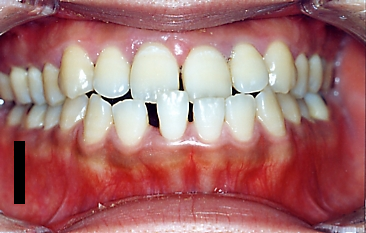

受け口セットバック手術の症例

症例 1

| BEFORE | AFTER |